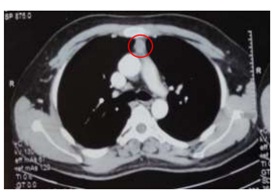

To locate ectopic source of ACTH, CECT (chest, abdomen and pelvis) was also done5 and the scans showed chest infection with bronchiectatic changes,? slight contrast enhancing lesion in thymus area and no adrenal glands enlargement.

The second CECT stated features suggestive of thymoma (2.1 x 2.0 x 2.7 cm), most likely malignant thymoma (benign lesion is less likely), pulmonary nodule on posterobasal segment of left lower lobe (DDx: infective or metastatic nodule), left pleural effusion and bilateral diffuse adrenal enlargement suggestive of adrenal hyperplasia.